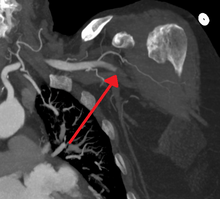

Acute occlusion of the axillary artery resulting in an ischemic limb as seen on CT angiography

In order to treat acute limb ischaemia there are a series of things that can be done to determine where the occlusion is located, the severity, and what the cause was. To find out where the occlusion is located one of the things that can be done is simply a pulse examination to see where the heart rate can be detected and where it stops being sensed. Also there is a lower body temperature below the occlusion as well as paleness. A Doppler evaluation is used to show the extent and severity of the ischaemia by showing flow in smaller arteries. Other diagnostical tools are duplex ultrasonography, computed tomography angiography (CTA), and magnetic resonance angiography (MRA). The CTA and MRA are used most often because the duplex ultrasonography although non-invasive is not precise in planning revascularization. CTA uses radiation and may not pick up on vessels for revascularization that are distal to the occlusion, but it is much quicker than MRA.[1] In treating acute limb ischaemia time is everything.